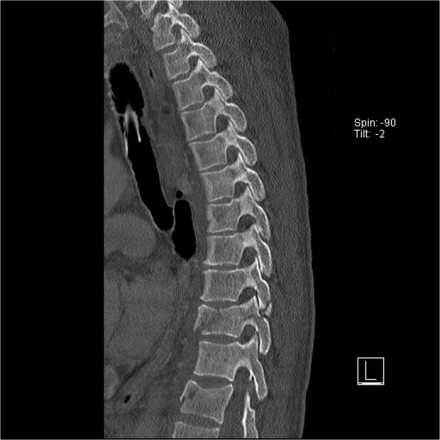

Look at the images.

What are the findings?

The findings are:

- Vertebral bodies show marrow edema as a result of a fracture.

- Torn flaval ligament (yellow arrow).

- Fractures through the posterior elements (red arrows).

The TLICS-score is high, because there is distraction and injury to the PLC.